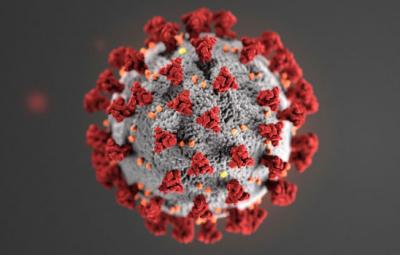

एकीकडे कोरोना व्हायरसच्या नव्या स्ट्रेनमुळे चिंता वाढली आहे. तर दुसरीकडे अजूनही कोरोना व्हायरसचे नवे साइड इफेक्ट समोर येत आहेत. कोरोनातून बरे झाल्यानंतरही अनेक लोकांच्या शरीरात कोरोनाचा प्रभाव बरेच दिवस बघायला मिळतो. ज्यामुळे त्यांना नव्या समस्यांचा सामना करावा लागतोय. मुंबईतील डॉक्टरांना काही वयोवृद्ध कोरोना व्हायरसच्या रूग्णांमध्ये नवीन इन्फेक्शन आढळून आलं आहे. हे इन्फेक्शन कोरोनामुळे पाठीच्या कण्यात होत आहे.